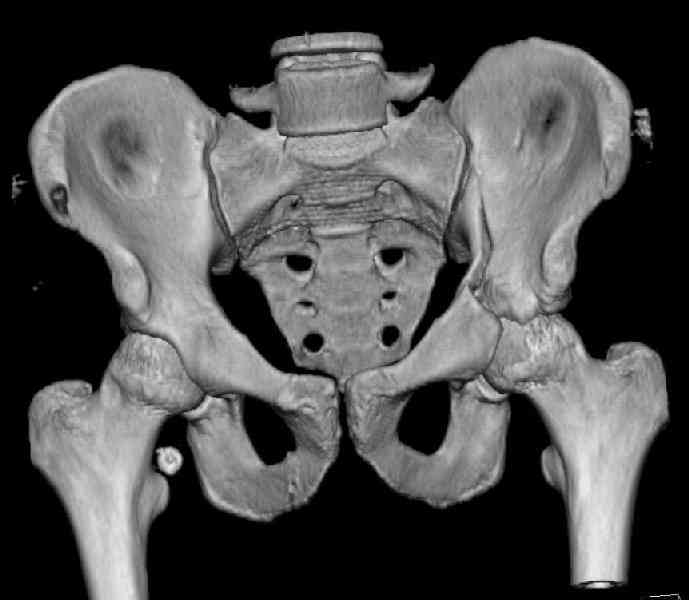

The last two images from the 3-D CT scan certainly makes the fracture look worse than the plan radiographs.

The joint is non-concentric as the head appears to be either "following the caudal segment", or the dome component is displaced from the tethered head... or so it seems... and he's young... so, many fracture surgeons would recommend reduction and fixation.

So we must decide preoperatively which part is the displaced segment?

It's difficult to know from these few selected images which component of the injury (was before and now) should be deemed the "soon to be mobile"

segment. It's my best guess that it is the caudal portion and there exists a healing fracture line somewhere thru the posterior column...one image

suggests it. If true, its early healing/union should be disrupted, and the resultant fragment mobility then allows accurate reduction.

Some more images. Does it help to guess which part of the acetabulum is displaced?

Normal appearing SI joints and a healed posterior column limb... my bet's on caudal segment displacement.